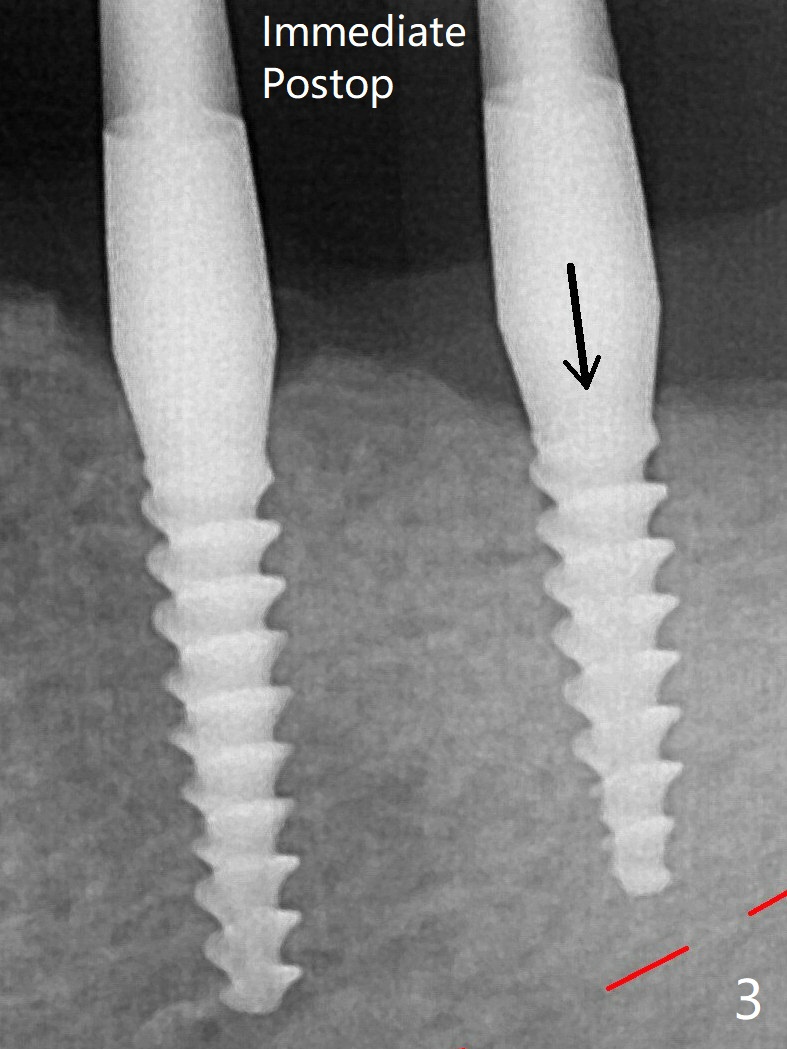

术后3.5月19牙位牙槽嵴吸收也严重(图九)。其实术后4个月19牙位牙槽嵴吸收并不严重(图十一)。